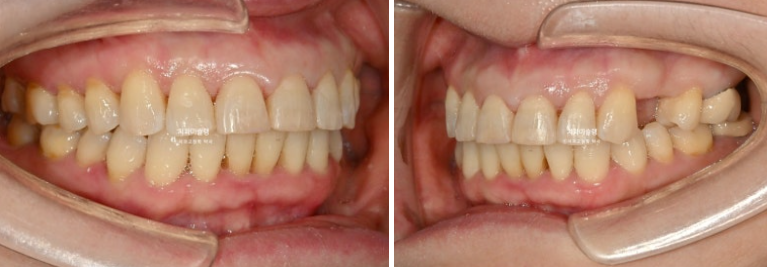

이제 전후 비교해보겠습니다.

24.07~26.01

앞니 각도의 개선이 눈에 띕니다.

아래 앞니는 치간삭제와 함입으로 위 앞니 사이사이 벌어진 공간을 이용하여 뻗친 각도와 골출을 개선하였으며

위 아래 앞니 각각 1.5-2mm 가량 뒤로 들어갔습니다.